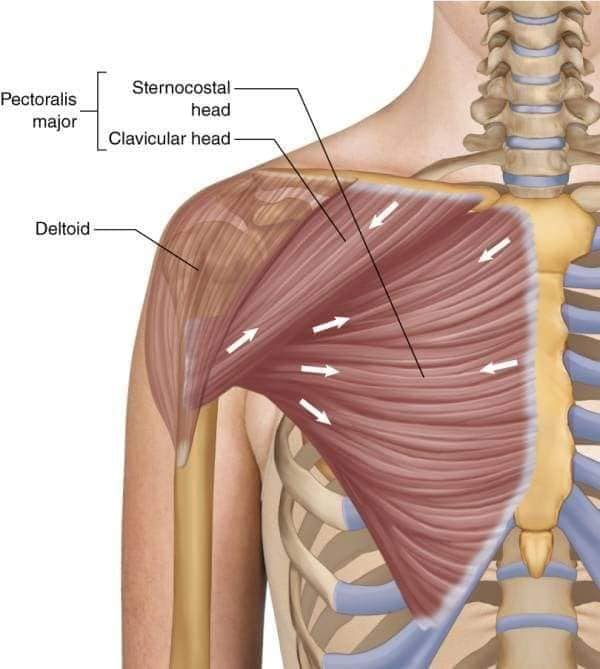

Поверхневі спинні м'язи

М'язи, що піднімають лопатку: Трапецієподібний м'яз: великий м'яз, що покриває верхню частину спини. Його функція - підтримка і рух лопаток, а також забезпечення стабільності хребта.

М'язи, що ведуть лопатку до хребта: Широкий м'яз спини: великий м'яз, що розташований в нижній частині спини. Він відповідає за рухи плечей і лопаток, а також за розширення верхньої частини тулуба.